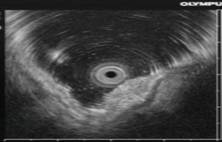

Ранний рак желудка. Общий эндосонографический критерий всех типов раннего рака желудка – это очаг неоднородного гипоэхогенного образования в пределах только слизистого слоя или занимающий слизистый и подслизистый слои стенки желудка (рис.1).

Рис.1. 62 года. Ранний рак верхней трети тела желудка.

Гистология – высокодифференцированная аденокарцинома:

а - визуальная картина РРЖ, подтип IIa; б – эндосонограмма РРЖ, подтип IIa, гипоэхогенное образование с признаками инвазии опухоли в подслизистый слой.